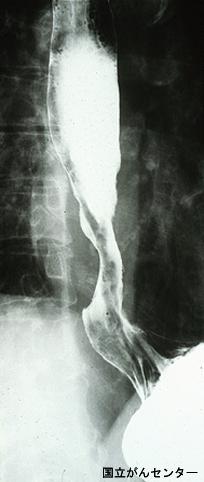

A case of type 3 advanced esophageal adenocarcinoma associated with Barret's epithelium in 1990's.

Tokyo Pref., Cooperative study between National Cancer Center and Kyushu Cancer Center

Malignant epithelial tumor/Adenocarcinoma

Esophagus/Lower third

X-ray

Type 3 Ulcerated type with infiltration/

40 -

serosa (adventitia)